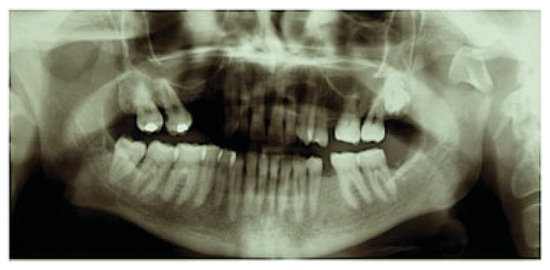

Development and Clinical Evaluation of MatrixMANDIBLE Subcondylar Plates System (Synthes)

Cortelazzi, R.; Altacera, M.; Turco, M.; Antonicelli, V.; De Benedittis, M. Development and Clinical Evaluation of MatrixMANDIBLE Subcondylar Plates System (Synthes). Craniomaxillofac. Trauma Reconstr. 2015, 8, 94-99. https://doi.org/10.1055/s-0034-1395382